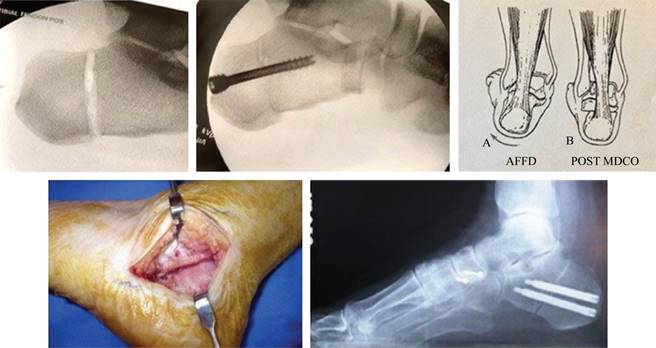

Los criterios para evaluar si la deformidad es elástica o no están en función, si el tendón es o no funcional y si la articulación subastragalina conserva o no su movilidad.123

Al ser un proceso evolutivo, en estadios previos (II y III) ya se empieza a asociar progresivamente, la rigidez del tríceps sural (gastrocnemio y/o sóleo), el acortamiento del tendón de Aquiles y la limitación de la flexión dorsal e inversión del pie.

A medida que el tendón tibial posterior pierde su función, el arco longitudinal medial se colapsa (estadio IV), lo que provoca una rotación interna relativa de la tibia y del astrágalo.37 Hay eversión de la articulación subastragalina que fuerza el talón en valgo y desviación de la articulación astragaloescafoidea, llegando a ser ineficaz la función del ligamento deltoideo.

A medida que la deformidad empeora, el peroné distal entra en contacto con el lateral del calcáneo, provocando dolor permanente en la parte posterior del pie.